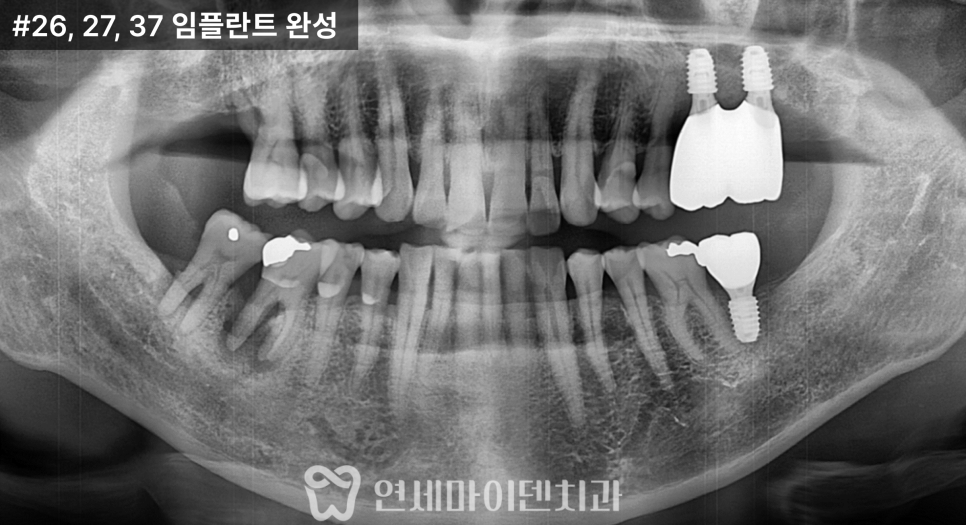

이번 케이스는

잇몸이 자주 붓고 출혈이 있으며,

고름이 반복되는 상태였습니다.

아래 어금니 한 부위

이미 크게 파절되어 있었고,

결과적으로

염증이 심한 두 개의 치아는 발치를 결정했고,

나머지 치아는 잇몸 치료를 통해

유지하는 방향으로 계획했습니다.

3개월의 치유 기간 후

맞춤형 지대주를 이용해

최종 보철을 완성했습니다.

치료 후 현재까지

잇몸뼈 레벨은 안정적으로 유지되고 있습니다.